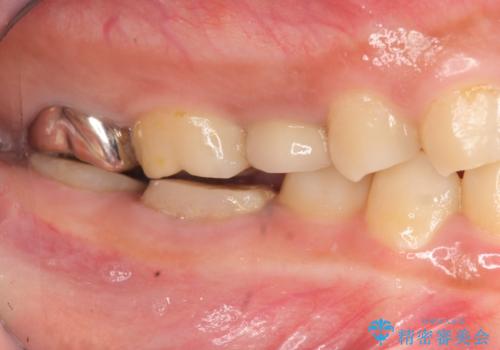

- 治療途中で放置してしまった奥歯の治療の続きを希望され来院されました。

奥歯は既に根管治療が為されクラウンを装着する必要性がある状態ですが、歯の高さが低くクラウンの安定性・強度を担保するために歯周外科を行う治療計画としました。

歯周外科を行うことで、歯ぐきの位置を下げ歯の高さを作り出し安定したクラウンの装着が可能となります。また同時に舌の邪魔となっていた骨隆起の除去を行うこととしました。